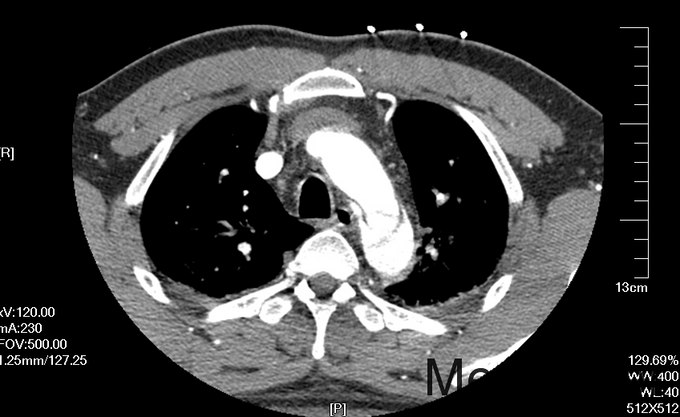

入院查体:体温36.5℃,脉搏90次/分,规则,呼吸18次/分,规则,血压150/80mmHg,胸廓正常,无胸骨叩痛。呼吸运动正常,语颤正常,无胸膜摩擦感,无皮下捻发感,叩诊正常清音,肺下界正常,双肺呼吸音粗,呼吸音对称,无罗音。心音可,心率90次/分,无杂音,腹部无压痛,无反跳痛,肝肋下未及,胆囊无压痛,Murphy征阴性,脾肋下未及,肾区无叩痛,双下肢不肿。入院后完善相关检查(胸腹主动脉CTA:主动脉夹层动脉瘤;两侧胸腔少量积液。)

予以诊断:1.主动脉夹层动脉瘤;2.高血压3级,极高危组。诊断明确后行“左颈总动脉-腋动脉转流手术+胸主动脉覆膜支架腔内隔绝术”。左侧颈部切口,游离出左侧颈总动脉,左侧锁骨下动脉,左侧椎动脉等分支。使用8mmG-tex血管一端与左锁骨下动脉行端侧吻合,G-tex血管另一端与左侧颈总动脉行端侧吻合。经右侧股动脉入路造影见主动脉夹层,破口位于左锁骨下动脉开口医院0.5cm处。左锁骨下动脉近端封闭,桥血管通畅,腋动脉及左侧椎动脉血流良好。置入美敦力胸主动脉覆膜支架(28*157mm),定位后释放。造影见胸主动脉支架释放良好。

主动脉夹层为大血管急诊,B型主动脉夹层相对预后良好。保守治疗效果尚可,近期死亡率相对不高。但对于年轻患者,我们积极治疗。患者B型主动脉夹层,破口位于锁骨下动脉附近。拟行腔内修复术。但患者破口离锁骨下动脉较近,若直接封闭,可影响左上肢活动及椎动脉顺行血流。故根据患者情况行一期复合手术(即“左颈总动脉-腋动脉转流手术+胸主动脉覆膜支架腔内隔绝术”)。术后复查可及左侧锁骨下动脉通畅,血流灌注可。可及假腔内明显血栓化。